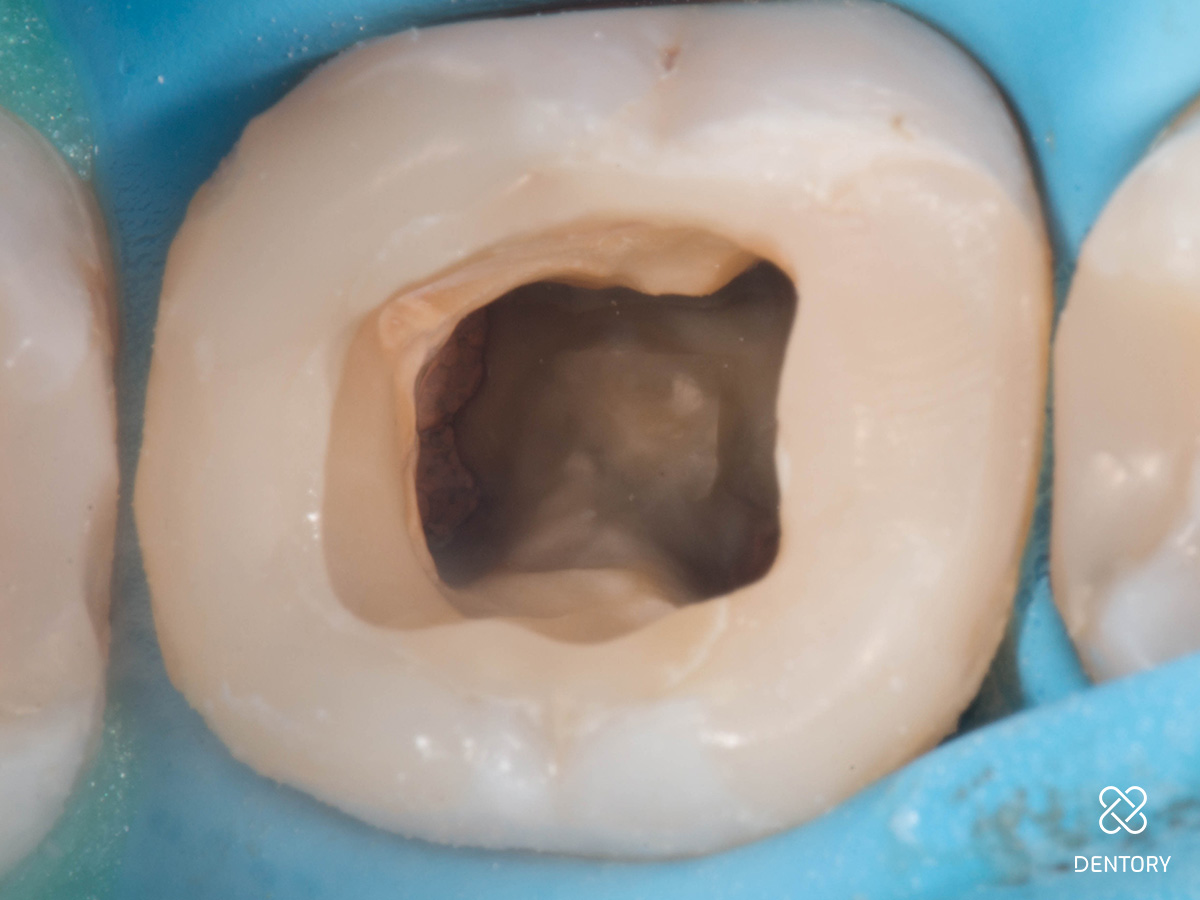

Abbildung 7

Zweite Sitzung: Zentral ist der temporäre Verschluss im Prä-Endo-Aufbau sichtbar.